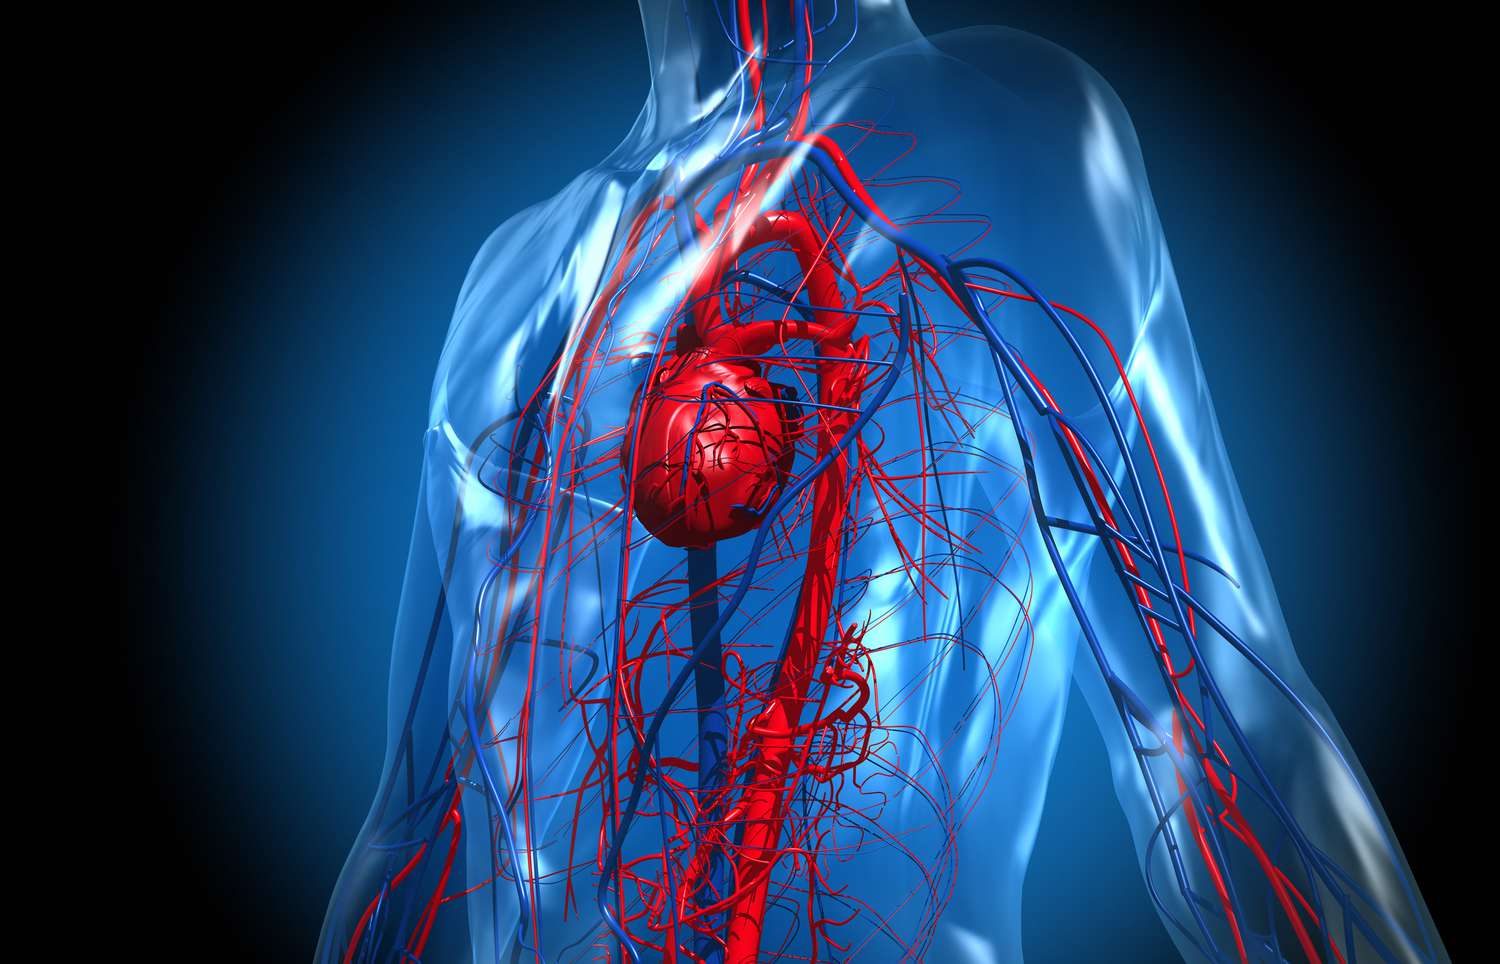

از دست دادن خون باعث کاهش حجم خون در بدن میشود و فشار خون پایین میآید. این وضعیت میتواند علائم زیر را ایجاد کند:

💬 «کمبود خون فوری نیاز به درمان اورژانسی دارد، زیرا قلب و مغز نمیتوانند به درستی اکسیژن دریافت کنند.»

کمبود شدید خون یا شوک ناشی از خونریزی میتواند مشکلات جدی ایجاد کند:

- آسیب اندامهای حیاتی مانند قلب و کلیه